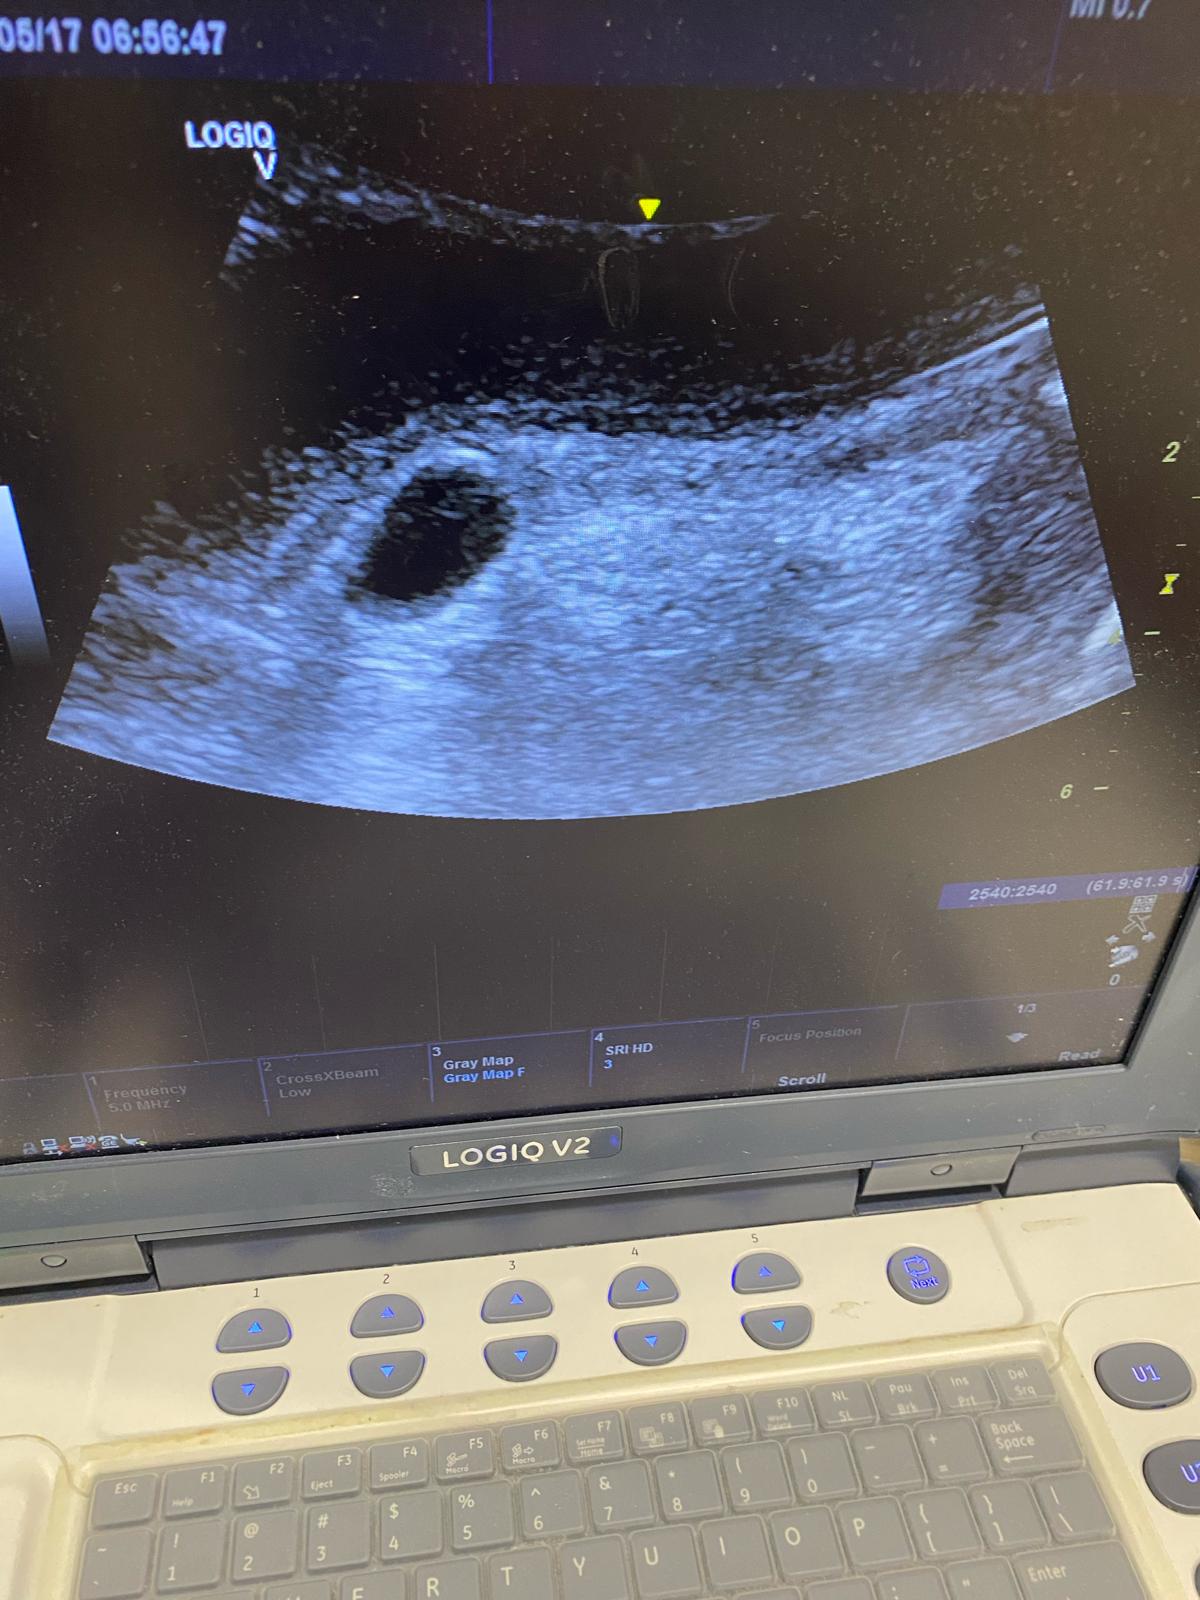

Vejiga distendida alcanzando mesogastrio, sin observar en su interior el balón de la sonda vesical. Al continuar la exploración, realizamos un corte longitudinal de la uretra peneana en el que podemos observar el balón de la sonda vesical en la parte proximal de la uretra.

Se concluyó anuria de causa obstructiva a nivel de uretra peneana por balón vesical mal posicionado.

Se desinfló el balón y se avanzó la sonda, bajo control ecográfico, hasta vejiga, recuperando una buena diuresis.